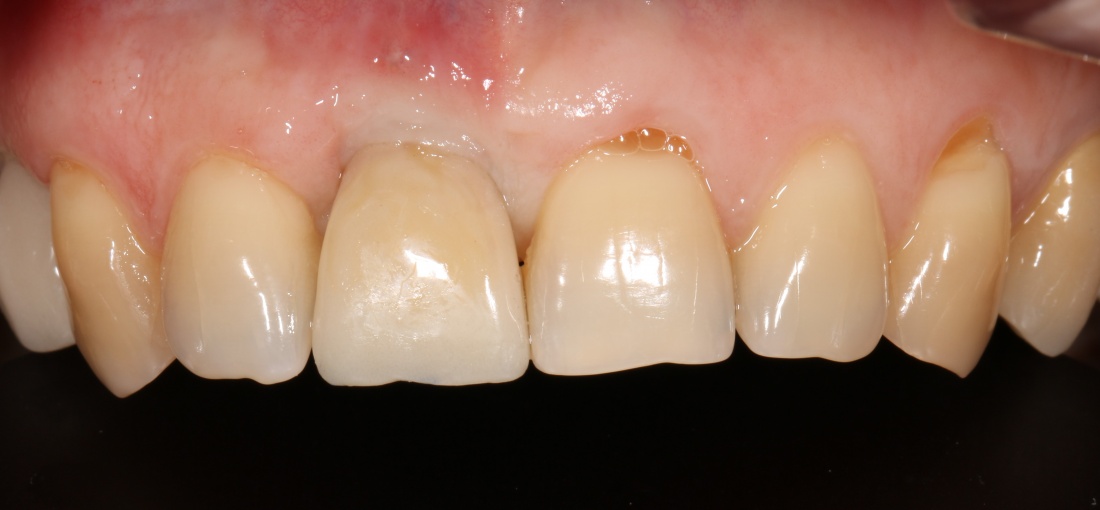

Недавно мой коллега Андрей Карнеев опубликовал в Facebook фотографию одной работы на финишных этапах протезирования:

которая через три месяца, к моменту интеграции импланта, выглядит совсем иначе:

Ну и… к моменту установки постоянной коронки, у нас сохранился естественный контур прилегающей десны.

Что, собственно, нам и требовалось сделать.